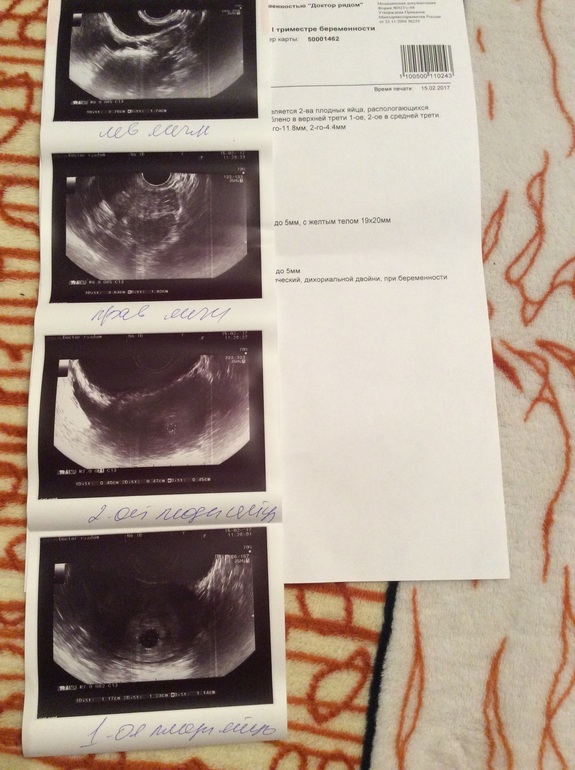

В итоге, имеем 2 плодных яйца. Одно на 6 недель и с сердцебиением, другой на 4 недели и пока ничего там нет. Я пыталась уточнить точно ли это второе плодное яйцо, мало ли. Врач меня заверила, что их там двое. Но как будет развиваться второй пока не известно, за неделю должно решиться. Первый день последних М был 26.12, то есть сегодня 7+3 нед

Может у кого-то было что-то подобное? Ведь все наладится и второй догонит первого? А если нет? Тогда как быть? На всякий случай прикреплю УЗИ, правда фото не поворачивается